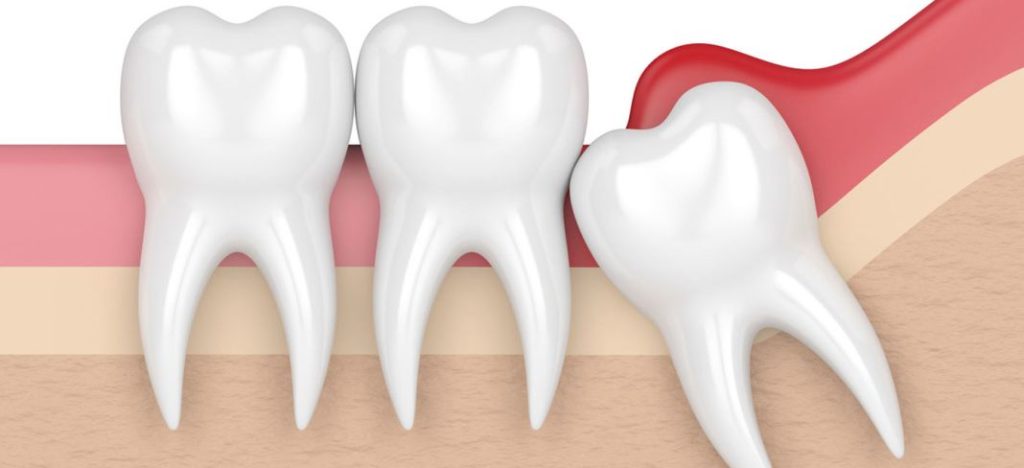

La aparición de las muelas del juicio puede provocar diversos problemas dentales. Debido a la falta de espacio en la mandíbula, las muelas del juicio pueden erupcionar parcial o completamente impactadas, es decir, que no pueden salir completamente de las encías.

Esto puede causar dolor, inflamación e infección. Además, las muelas del juicio también pueden ejercer presión sobre los dientes adyacentes, causando apiñamiento y desalineación dental.

Como resultado, muchas veces no hay suficiente espacio en la boca para que las muelas del juicio erupcionen correctamente. Esto puede causar que las muelas del juicio se impacten o queden atrapadas en el hueso o las encías, lo que puede ser doloroso e incluso causar infecciones.

Cuando las muelas del juicio no tienen suficiente espacio para salir, pueden quedar impactadas en la mandíbula o en las encías. Esto puede causar dolor, hinchazón, infecciones y daño a los dientes vecinos, lo que hace que la extracción sea necesaria en muchos casos. Las muelas del juicio impactadas también pueden causar la formación de quistes o tumores en el área afectada.